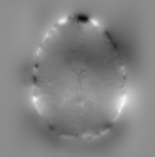

Refer to captionRefer to captionRefer to captioninitializationOptimal TransportRefer to captionRefer to captionRefer to captionOptimal Transport (blurred)Refer to captionRefer to captionRefer to captionMultilevelRefer to captionRefer to captionRefer to captionoptimizedRefer to captionRefer to captionRefer to captionRefer to captionRefer to captionRefer to caption

Figure 6: Example field maps (Subject ID 826353) at initialization (top row) and after optimization with Gauss-Newton (bottom row). The first column uses the proposed optimal transport initialization scheme. The middle column uses the same scheme with an additional Gaussian blur to promote smoothness. The right column uses the coarse-to-fine multilevel initialization scheme from HySCO with five levels, and the final field map is optimized at the original image resolution. The multilevel initialized field map is smooth by construction and further optimized to improve the relative image distance at the full resolution. The optimal transport initialization accurately corrects the distortions but is not smooth in the non-distortion dimensions unless blurred with a Gaussian. After the fine-level optimization all field maps are visually similar.